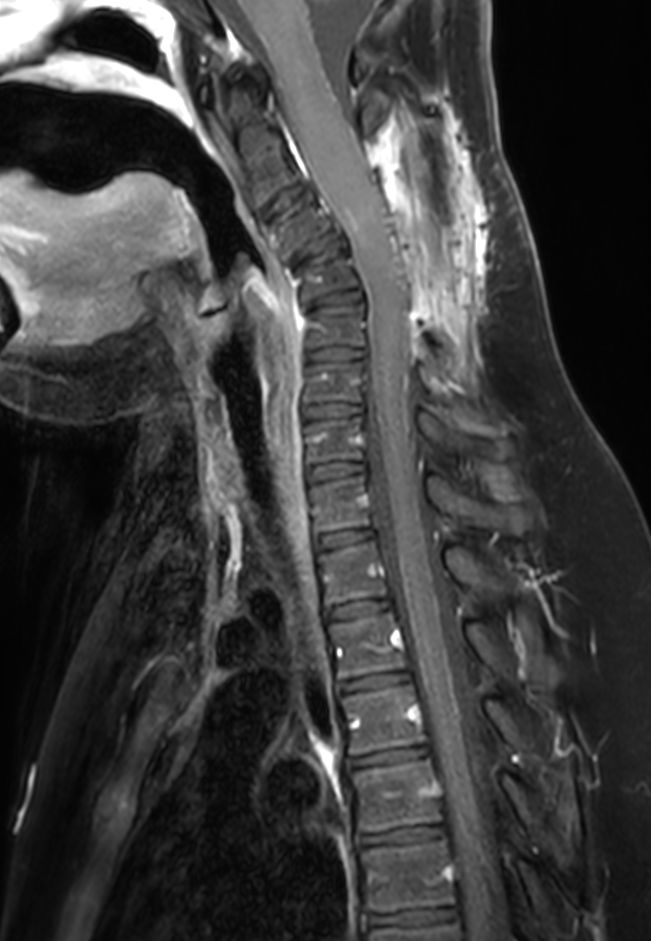

Sagittal T2w TSE (C-Spine)